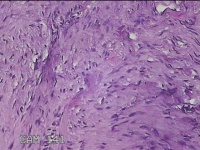

左耳赘生物

性别

女

年龄

23岁

临床诊断

纤维瘤?

一般病史

左耳皮肤起新生物2年。

标本名称

大体所见

灰白暗红色组织1.8x1.5x0.7cm,表面光滑,切面灰白粉红色,质软。

图2

良性病变。